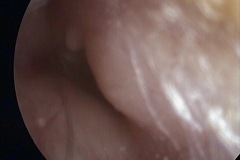

Perforation

Tympanic Membrane